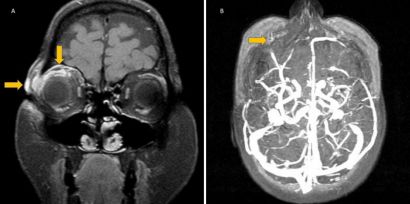

Stingray tails may cause significant ocular injury. The stingray's barbed tail spine can penetrate into soft tissue, causing damage via physical trauma, the venomous nature of the spine, and inoculation by marine bacteria.[38] Therefore, empiric antibiotics should be initiated. One report described a stingray tail injury that caused orbital cellulitis and superior optic vein thrombosis (Figure 5), so these complications should be kept in mind as well.[38]